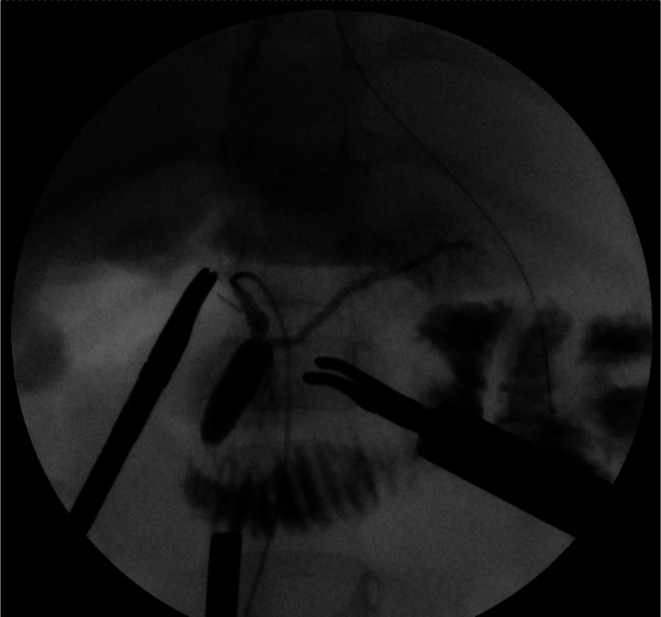

Fresh frozen plasma was administered to correct coagulopathy immediately after admission, and the patient underwent emergency robotic surgery using the da Vinci Xi surgical system 6 h later. A Benz incision was made at the umbilicus to insert a multichannel port with additional robotic ports placed, following our conventional approach [ref. 4] (Figure 2). Bile‐stained ascitic fluid was observed. The hepatoduodenal ligament was inflamed and adhered to adjacent structures, including the duodenum, colon, and greater omentum. Initial adhesiolysis was performed laparoscopically, followed by robotic docking (Supporting Information: Video). Dissection of the common bile duct revealed a perforation on its anterior wall. The distal bile duct was mobilized into the pancreas without difficulty. Intraoperative cholangiography revealed a protein plug in the common channel with poor contrast passage into the duodenum, which improved after repeated irrigation (Figure 3). The bile duct was transected approximately 5 mm proximal to the common channel junction. Proximal dissection up to the hepatic hilum revealed no strictures. The right hepatic artery runs anterior to the common hepatic duct; the duct was successfully mobilized anteriorly to this vessel. A Roux‐en‐Y jejunal limb was prepared via an umbilical incision, and hepaticojejunostomy was completed robotically using 5–0 absorbable monofilament sutures with single knots via retrocolic route. A drain was placed behind the anastomotic site.